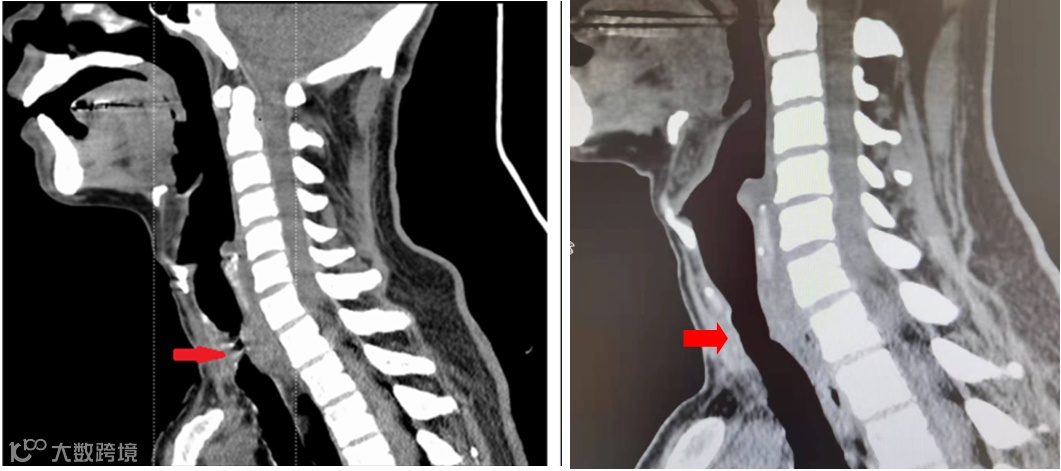

治疗前后影像对比

最终,手术很顺利,效果立竿见影。术后当天,阿德的喘憋症状就基本消失了,术后复查CT,气道由4mm扩张至9mm。对这名病例的成功救治意味着宝安区中心医院在呼吸介入治疗方面已经走在了国内前列,对此类危重症患者的救治有了更多的选择和保障。